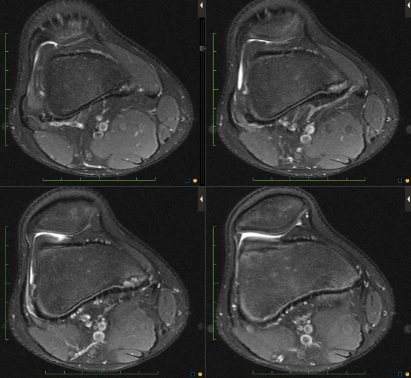

Figure 2 for case Cortical desmoid

Figure 2